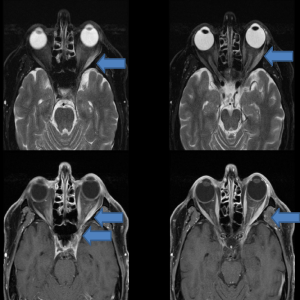

The patient’s MRI revealed an increased T2 signal with abnormal enhancement within the left lateral rectus muscle and intraconal fat extending into the orbital apex and left cavernous sinus.